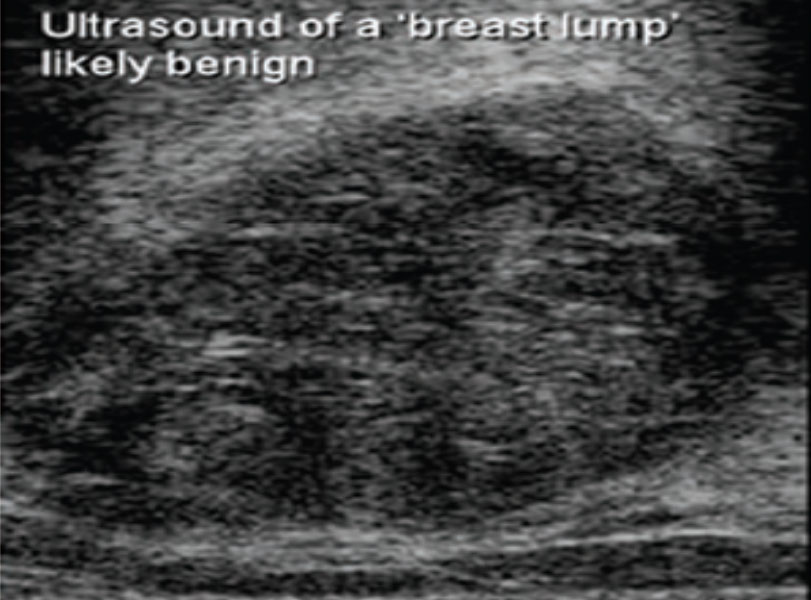

பொதுவாக மார்பக கட்டிகளில் 80% சாதரண கட்டிகள் ஆகும், 20 % களில் மட்டுமே புற்றுநோய் கட்டிகள் ஆகும்.

செவியிணரா ஒலி மற்றும் மேம்மோகிராம் எனப்படும் அதி நவீன எக்ஸ்ரே உதவி கொண்டு மார்பக கட்டிகள் பரிசோதிக்கப்படுகிறது.

மார்பக கட்டி அணுக்கள் பரிசோதனை (Fine Needle Aspiration Cytology , Trucut Biopsy )

மார்பக கட்டிகளில் செல்கள் மற்றும் திசுக்கள் ஊசி மூலம் எடுக்கப்பட்டு நோய் குறியியல் மருத்துவரால் பரிசோதிக்கப்படுகிறது.